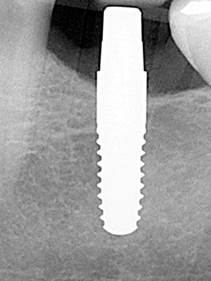

Desde los años setenta se intenta fabricar implantes dentales libres de metal con la ayuda de materiales cerámicos. Un gran avance se consigue con las máquinas de fresado guiado por ordenador CAD/CAM capaces de trabajar la extrema dureza de la cerámica dióxido de circonio.

Hasta hace poco tiempo solo existían implantes de cerámica de una sola pieza por razones técnicas. Para el implantólogo es más difícil y requiere más práctica colocar este tipo de implantes en su posición óptima. El diagnóstico en 3D es una ayuda importante para lograrlo. En los primeros 2 meses, mientras se produce la osteointegración del implante, el profesional tiene que buscar para cada caso la mejor forma para proteger el pilar del implante que sobresale de la encía contra fuerzas que puedan provocar micro movimientos del implante que harían fracasar la correcta integración, es decir, la pérdida del implante. Además, el paciente tiene que tener especial cuidado, como por ejemplo no masticar en el lado del implante insertado. Con el avance tecnológico, ya es posible contar con implantes de circonio de dos piezas parecidos a los implantes de titanio. Parece que los resultados clínicos son favorables y nos permite simplificar el protocolo.